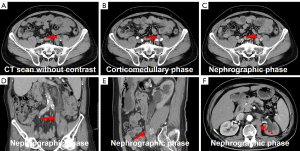

After completing six cycles of chemotherapy consisting of bevacizumab (400 mg) on day 1 + paclitaxel (300 mg) on day 1 + gemcitabine (1.6 g) on days 1 and 8, the patient underwent a follow-up CTU. The results revealed a significant reduction in the size of the ureteral lesion and metastatic lymph nodes compared to the previous scan (Figure 6), with the treatment efficacy evaluated as partial remission (PR). Subsequently, the patient received whole abdominopelvic intensity-modulated radiotherapy (62.5 Gy/25 fractions/5 weeks). One month later, urologic magnetic resonance urography (MRU) demonstrated a marked reduction in the size of the lesion (Figure 7). As of this writing, the patient is currently alive and well and continues to be under regular follow-up.